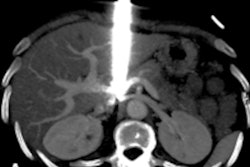

CT's diagnostic accuracy makes it a good candidate for trauma imaging, and the development of whole-body CT makes it even more attractive. However, the use of WBCT -- encompassing a scan of the head, cervical spine, chest, abdomen, and pelvis -- remains controversial due to the additional radiation dose it delivers to patients, which can reach up to 20 mSv, the team noted.